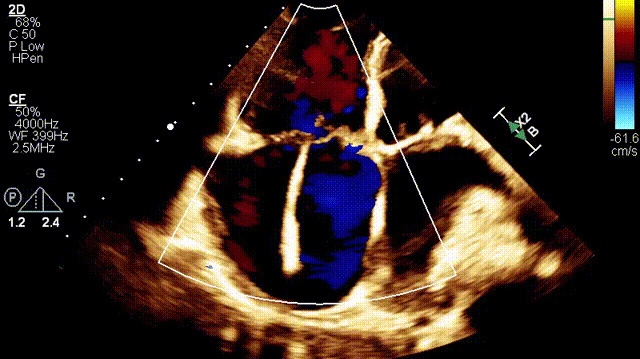

植入前超聲

手術(shù)在全麻狀態(tài)下開展,此次手術(shù)采用經(jīng)右側(cè)頸靜脈入路的方式將輸送器送入患者心臟內(nèi),在TEE及DSA引導(dǎo)下調(diào)整輸送器頭端角度,使得輸送器與三尖瓣瓣環(huán)平面垂直。在輸送器進(jìn)入右心室后釋放室間隔錨定裝置,而后釋放瓣葉夾持件(2個(gè)耳片結(jié)構(gòu))成垂直狀態(tài)。在TEE及DSA確定夾持件固定至三尖瓣葉根部且位于右室側(cè)后釋放人工瓣心房側(cè)盤片。隨后調(diào)整瓣膜同軸性以及室間隔錨定件位置(貼合室間隔),前推藏針管并固定,進(jìn)而釋放室間隔錨定裝置,并再次確認(rèn)瓣膜位置、穩(wěn)定性及同軸性,合攏輸送鞘后撤出輸送器,完成LuX-Valve Plus人工三尖瓣瓣膜的植入。